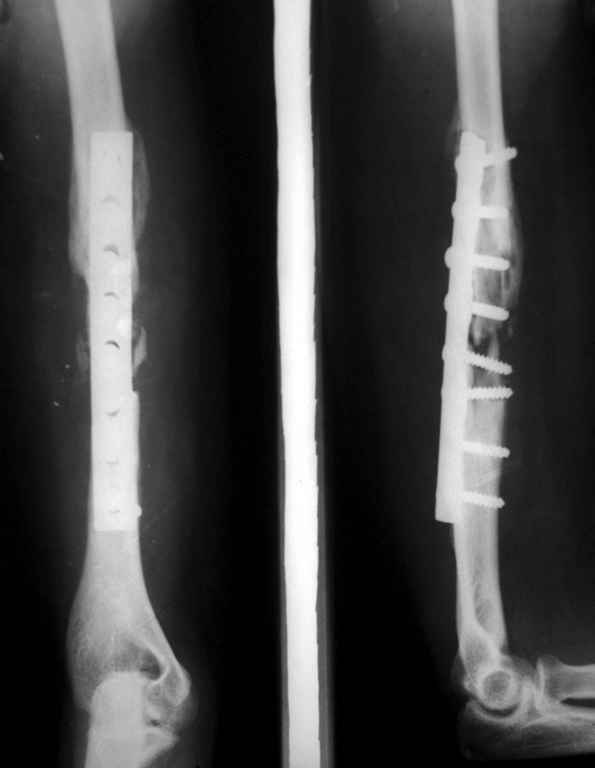

Владимир. Выделяем свои малоберцовую кость практически полность. Выпиливаем замок там и тут. Синтез. Нетипичный случай, но перестраивается хорошо даже диафиз. С уважением Дрягин